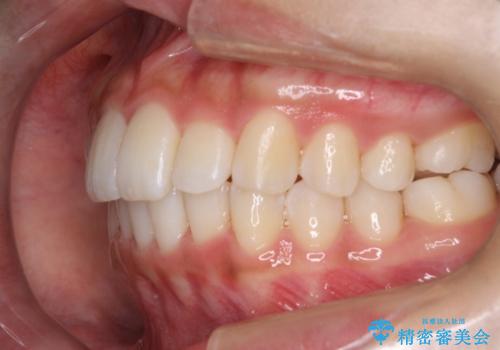

Invisalign インビザラインによる軽度なガタつきの改善

- 奥歯の位置関係はそこまで大きくいじらず、前歯群のみでガタつきの改善を計画しました

奥歯の位置関係に改善の余地はありますが、機能的に問題のない cusp to fossa の関係で咬めているため、前歯のガタつきを前歯のみで改善するというシンプルな計画で、短期間で治療を終了させました。